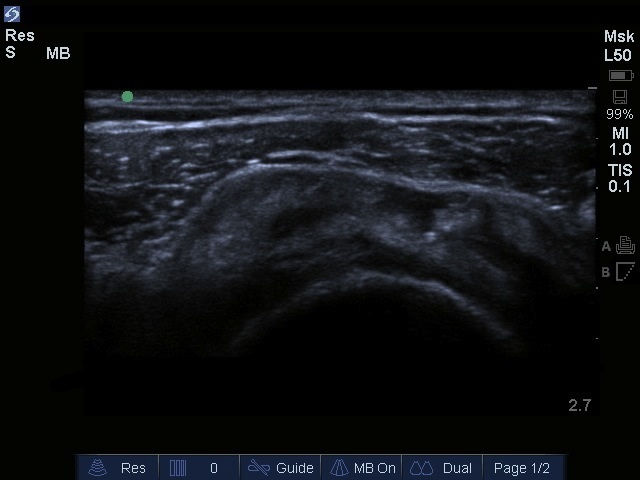

Bild: Rotatorenmanschettenruptur an der Schulter, transversal